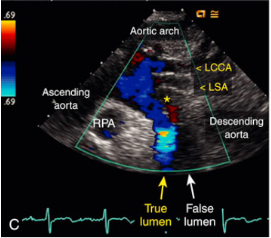

Aortic dissection

What is seen in this 2D image at the SSN?

To-and-fro pattern

Secondary communication points

What is this spectral Doppler pattern called?

Where is it found in regards to aortic dissection?